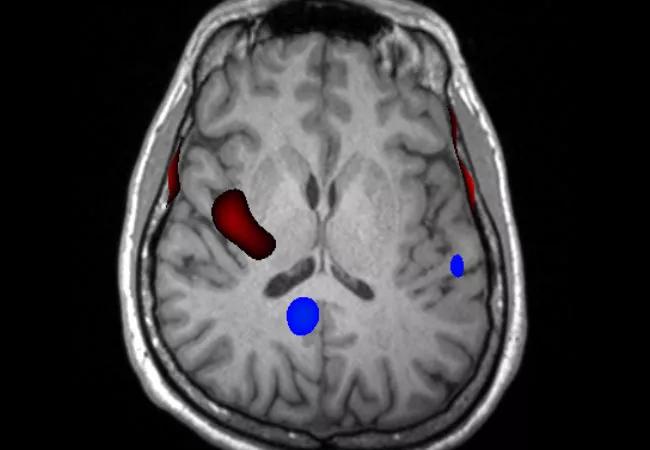

Ictal SPECT was performed with injection 23 seconds after seizure onset. Areas of hyperperfusion (red coloring in the image below) were found in the right mid-posterior superior insula.

Magnetoencephalography (MEG) was performed in an attempt to further localize the patient’s epilepsy. It revealed dipole clusters in the dorsolateral, mesial central and superior parietal regions of the right hemisphere, as shown in the image below.